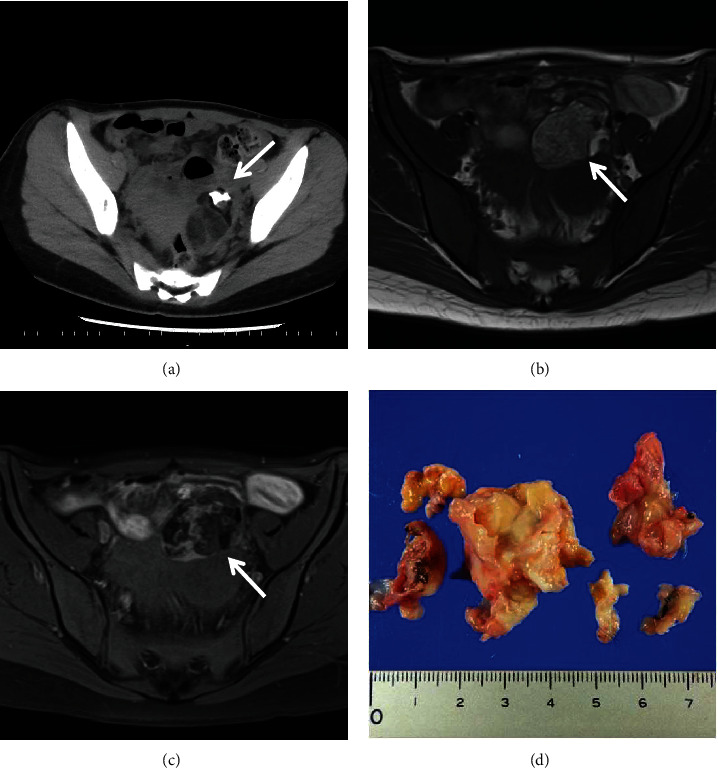

Background: Autoimmune hemolytic anemia (AIHA) associated with solid tumors such as mature cystic teratomas is rare and poorly understood. Here, we report a successfully treated case of secondary AIHA in a mature cystic teratoma containing antibodies against red blood cells. Case description. A 22-year-old woman was referred to our hospital with progressive anemia. Laboratory findings revealed hemolysis with a positive direct and indirect antiglobulin test. Imaging studies identified a left ovarian mass, suspected to be a mature cystic teratoma, which was later confirmed by histopathology after laparoscopic oophorocystectomy. The patient was treated with prednisolone, resulting in improved anemia. To examine the relationship between the tumor and AIHA, an indirect antiglobulin test was performed on the tumor contents. Stronger aggregations were observed at any concentration diluted by 10 times from 10 to 10,000 times of the tumor contents compared to the patient's serum. Additionally, immunofixation electrophoresis of the tumor contents revealed the presence of monoclonal immunoglobulin G-κ.

Conclusion: The presence of monoclonal IgG-κ in the tumor suggests intratumoral antibody production as a possible mechanism. Further research is necessary to elucidate the pathogenic relationship between such tumors and AIHA. The report also highlights the importance of considering secondary AIHA in patients with unexplained anemia and solid tumors.